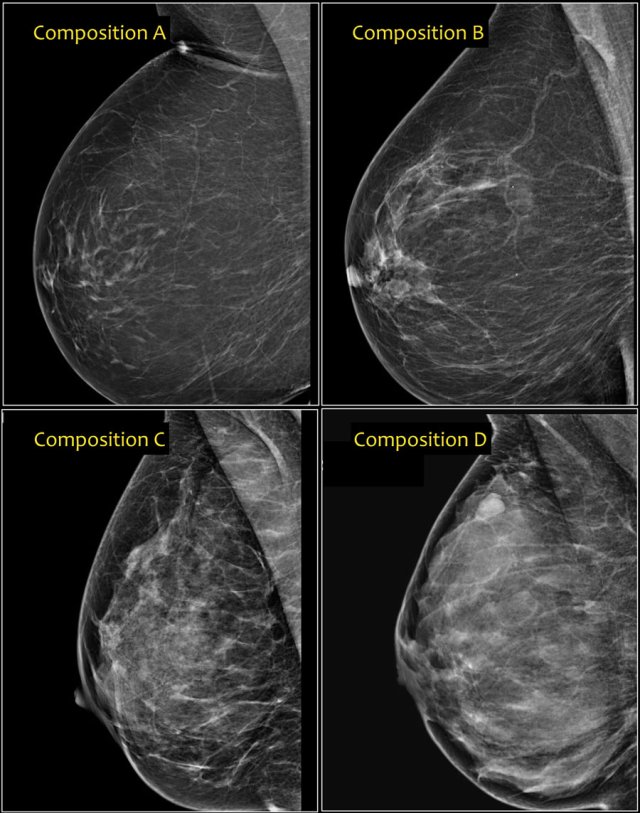

In the BI-RADS edition 2003 the assignment of the breast composition was based on the overall density resulting in ACR catergory 1 ( <25% fibroglandular tissue), category 2 ( 25-50%), category 3 (50-75%) and category 4 (>75%).

In BI-RADS 2013 the use of percentages is discouraged, because in individual cases it is more important to take into account the chance that a mass can be obscured by fibroglandular tissue than the percentage of breast density as an indicator for breast cancer risk.

In the BI-RADS edition 2013 the assignment of the breast composition is changed into a, b, c and d-categories followed by a description:

- a- The breast are almost entirely fatty.

Mammography is highly sensitive in this setting.

- b- There are scattered areas of fibroglandular density.

The term density describes the degree of x-ray attenuation of breast tissue but not discrete mammographic findings.

- c- The breasts are heterogeneously dense, which may obscure small masses.

Some areas in the breasts are sufficiently dense to obscure small masses.

- d - The breasts are extremely dense, which lowers the sensitivity of mammography.

Notice in the left example the composition is c - heterogeneously dense, although the volume of fibroglandular tissue is less than 50%.

The fibroglandular tissue in the upper part is sufficiently dense to obscure small masses.

So it is called c, because small masses can be obscured.

Historically this would have been called an ACR 2: 25-50% density.

The example on the right has more than 50% glandular tissue and is also called composition c.